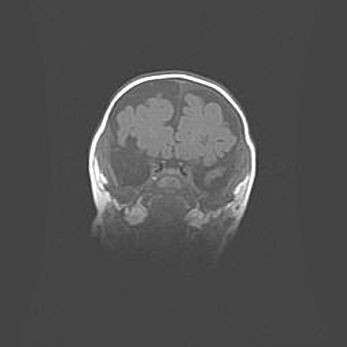

Мальформация Денди-Уокера. Киста задней черепной ямки.

Агенезия мозолистого тела.

Возраст: 2,5 месяца

Вес: 2420 г

Пол: женский

Окружность головы: 37 см

Срок гестации: 32 недели

Мальформация Денди—Уокера — редкий вид патологии ЦНС, представляющий собой врожденный порок развития каудального отдела ствола и червя мозжечка, ведущий к неполному раскрытию срединной (Мажанди) и латеральных (Лушка) апертур IV желудочка мозга. Для этогно синдрома характерна триада симптомов: гипотрофия червя мозжечка и/или полушарий мозжечка, кисты задней черепной ямки, гидроцефалия различной степени. В 70% случаев порок сочетается и с другими аномалиями головного мозга, в частности с агенезией мозолистого тела.